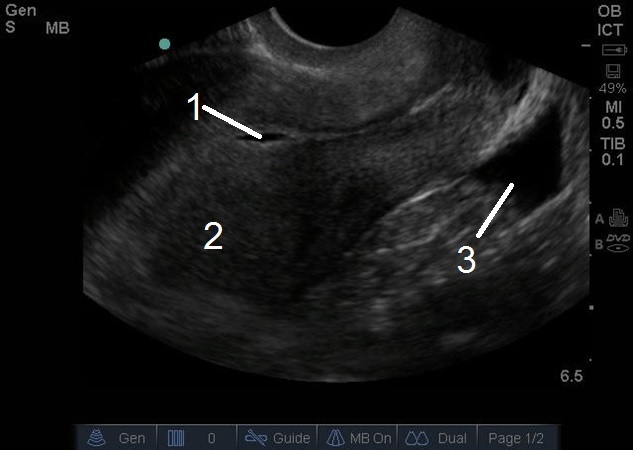

Bild: Transvaginaler (TV) Ultraschall des Beckens, ektopische Schwangerschaft, Pseudo-Fruchtblase, sagittal, freie Flüssigkeit

1. Pseudogestationssack

2. Leerer Uterus

3. Freie Flüssigkeit im rektovesikulären Raum, posterior